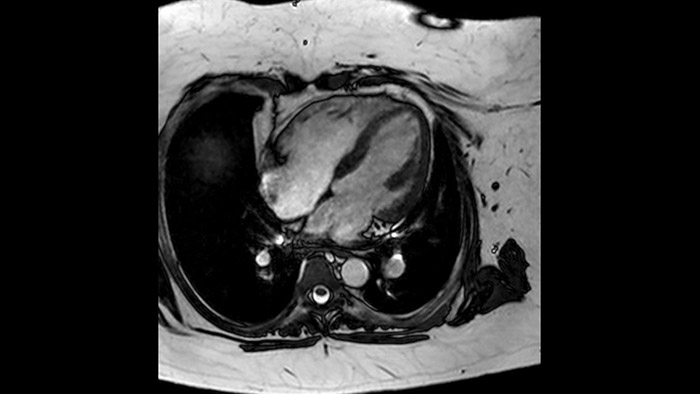

L'utilità diagnostica e prognostica della RM cardiaca è in continua crescita. È possibile valutare l'anatomia e la funzionalità cardiache utilizzando acquisizioni cine, ottenere informazioni sulla perfusione e vitalità del tessuto cardiaco, visualizzare potenziali edema con la sequenza Black Blood, accedere e persino quantificare la caratterizzazione dei tessuti con CardiacQuant.